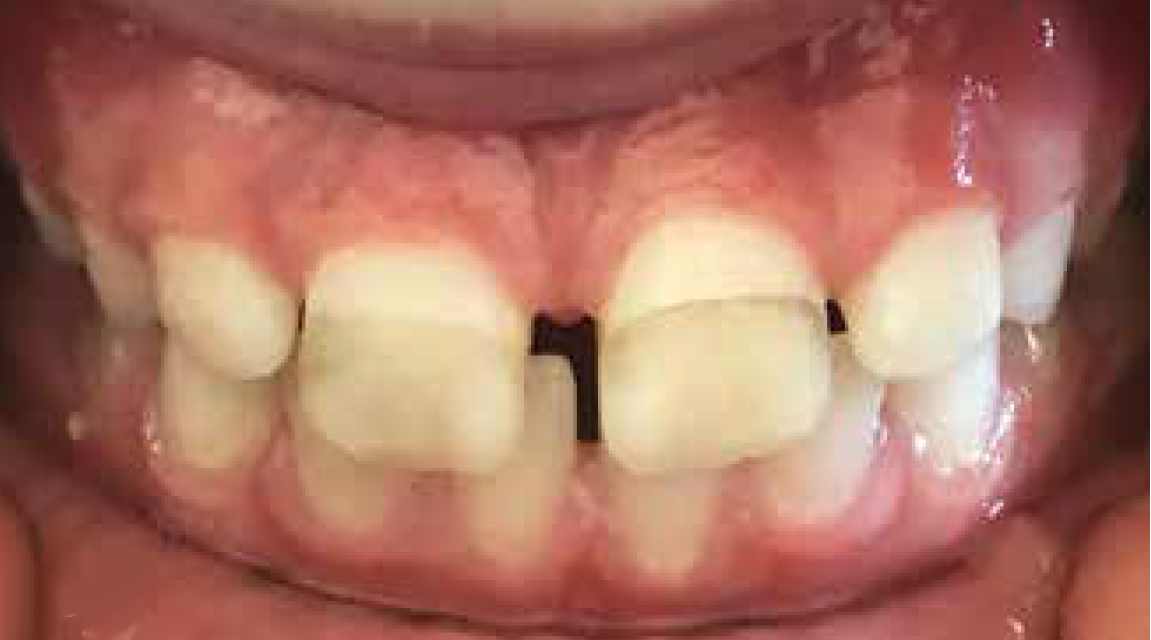

Application to erupting teeth in esthetic areas should be considered with caution. It is important to note that permanent teeth crowns can enter the mouth incompletely mineralized. While enamel always goes through a maturation process for years after eruption, in some patients (who do not have amelogenesis imperfecta) the emerging enamel is actually porous and takes at least a few weeks to close.29 This concern is compounded because enamel hypomineralization increases caries risk, and, thus, the children who would benefit most from the preventive effect are also at the highest risk for stain. Figure 3 shows an example of stain at the gingival margin when SDF was applied. The enamel surface gingival to the dark stain shows by contrast that all other exposed enamel may have been more subtly stained. The inciso-gingival thickness of the stain shows that the enamel was no longer susceptible to stain after being bathed in saliva for a few weeks.

Fig 3. SDF can stain erupting enamel. SDF was applied to the upper incisors while they were still erupting. The enamel at the erupting front (gingival margin) at the time of treatment was immature and porous. Significant amounts of silver penetrated into the enamel and oxidized, becoming apparent. The inciso-gingival extent of the stain shows that only the enamel that had erupted within the previous few weeks took up enough silver to become visible.